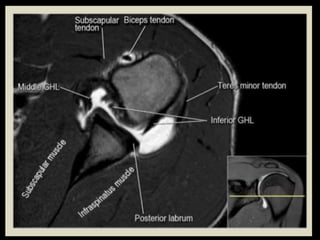

Shoulder

Joint.